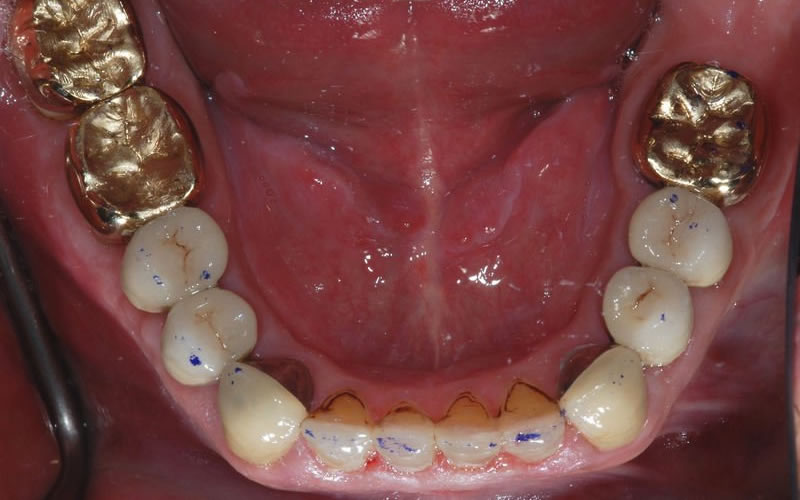

A Crown, also known as a Cap, can be made from porcelain or metal or a combination of both. They can also be made from gold.

Dental Crowns (7 images)